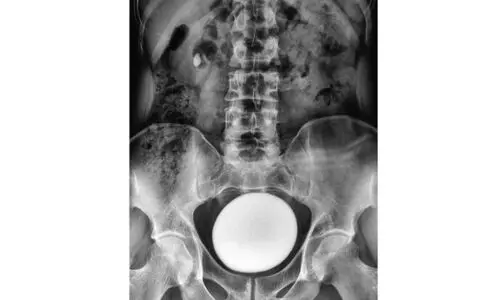

1) പ്രവാസികളിൽ മൂത്രാശയക്കല്ല് രോഗം വർധിച്ച തോതിൽ കാണുന്നതിന് കാരണമെന്താണ്●വെള്ളം കുടിക്കുന്നത് കുറയുന്നതാണ് പ്രവാസികളിൽ...